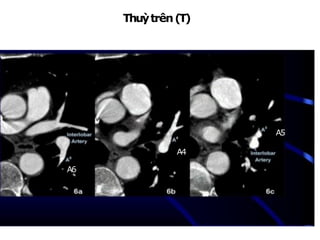

ĐỘNG MẠCH PHỔI (T)

Thuỳtrên(T)

NhánhA1+2:từ mặttrênĐMphổi (T)đi lêntrên

NhánhA3:đi ratrước

NhánhA4:lưỡi trên, từ mặttrước ĐM gianthuỳđi lên trên

A4

A5

A6

Thuỳdưới (T)

NhánhA6:từ ĐM gianthuỳngangmứchoặcngaytrênchỗ xuất

phátĐMthuỳlưỡi, đi rasau

Thuỳdưới(T):

NhánhA7+8:từ thân

đáy đi xuống,ra

trước, vào trong

NhánhA9:rangoài

NhánhA10:rasau

A9

A10

A8

A7